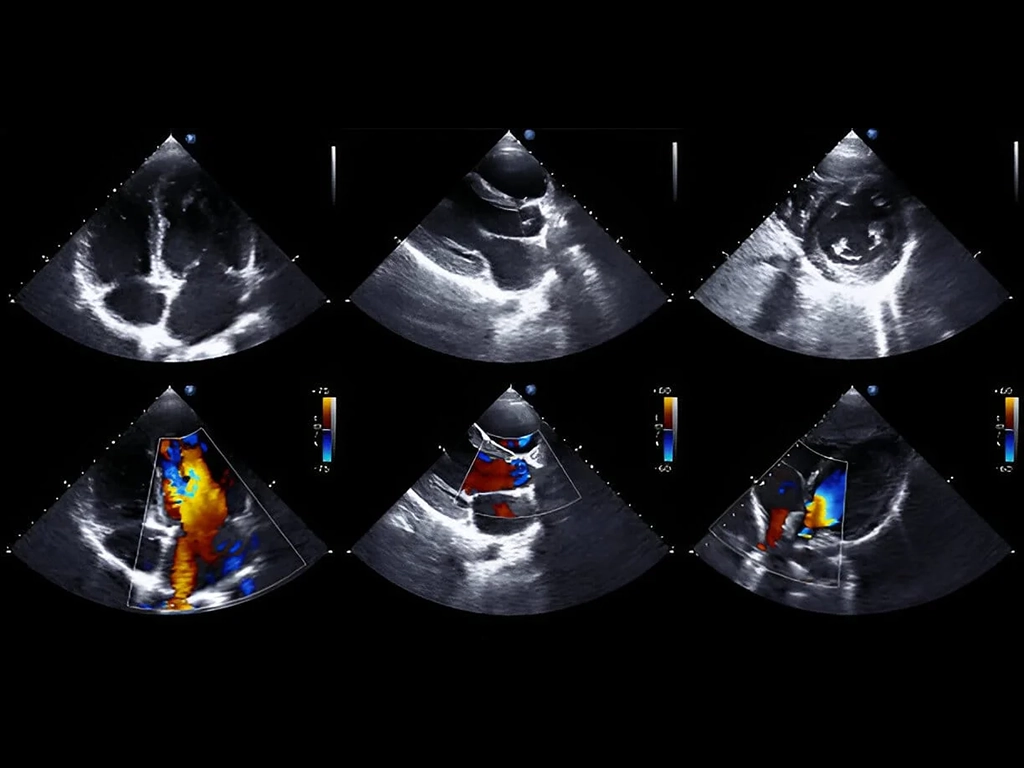

- اکو داپلر: برای سنجش سرعت و جهت جریان خون و برآورد شدت مشکلات دریچهای و فشار ریوی در همه انواع اکوکاردیوگرافی قلب به کار میرود.

اکو داپلر

تقریباً در همه انواع اکوکاردیوگرافی قلب از داپلر استفاده میشود تا سرعت و جهت جریان خون اندازهگیری شود. داپلر پیوسته برای جریانهای پرسرعت مانند تنگی دریچهها و داپلر پالسی برای جریانهای نقطهای به کار میروند. با این دادهها میتوان شدت تنگی یا نارسایی دریچهها و نیز فشار سیستولیک شریان ریوی را برآورد کرد. استانداردهای انجام این اندازهگیریها در راهنماهای تخصصی به تفصیل آمده است.